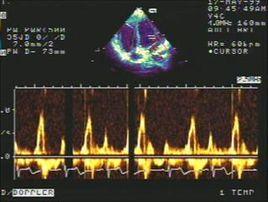

將取樣容積置於心臟大血管的不同部位,可獲得該部位的血流頻譜曲線,曲線橫軸代表時間,縱軸代表血流速度,從頻譜曲線上可以了解血流性質、方向、流速等。

頻譜都卜勒超聲心動圖分為脈衝都卜勒(pulsedwaveDoppler,PW)和連續都卜勒(continuouswaveDoppler,CW)兩種。頻譜都卜勒對血流的探測不是直觀的,通過頻譜的變化進而表達血流的改變,對血流的定量測定來說,頻譜都卜勒是必備的工具。